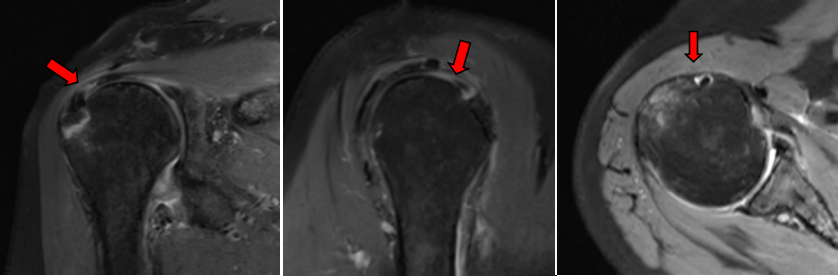

王某某,女,61岁,3个月前因摔伤致右肩部肿痛伴功能受限,于当地医院住院1周后因右肩部疼痛加重伴活动受限来我院就诊。行右肩MRI检查示:右肱骨大结节骨折,伴冈上肌腱部分撕裂、肩胛下肌腱损伤、肱二头长头肌腱炎、关节囊粘连。

肩袖撕裂常见于中老年人群,在肌腱退行性变的基础上,很容易发生损伤。病人常表现为肩部疼痛,严重时夜间痛醒,肩部上抬无力等。常常被误诊为肩周炎(冻结肩)。核磁共振检查可以发现肩袖的破裂口。